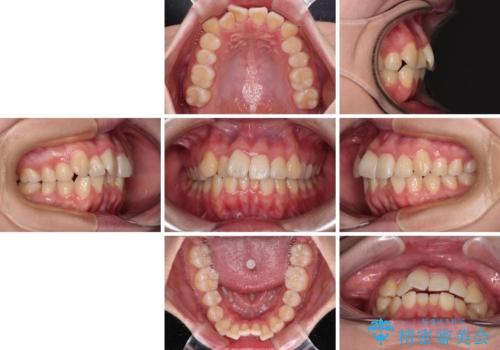

【モニター】八重歯を片側の抜歯矯正で治す メタルブラケット装置

- 八重歯とずれた正中を気にして来院された患者様です。

非抜歯矯正ではデコボコを解消することでより口元が突出する可能性があるため、上顎右右側の小臼歯1本の抜歯を行い、ワイヤー装置による矯正治療を行うこととしました。

正中位置を合わせるために、上顎臼歯部にアンカースクリューを埋入することとしました。